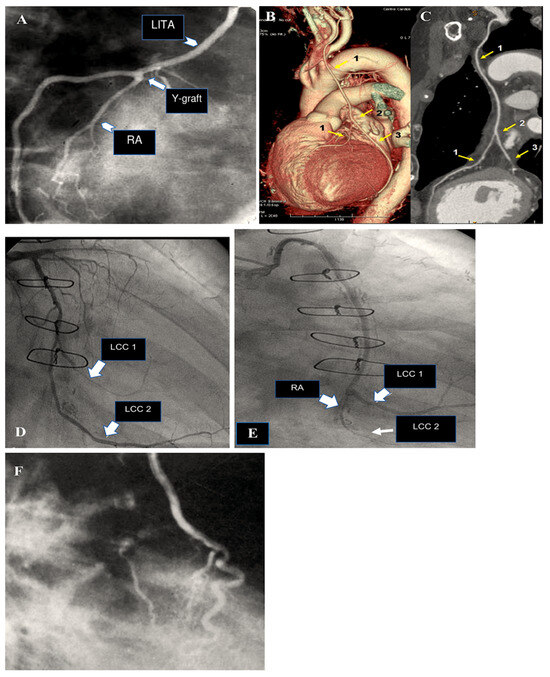

The results of a most recent investigation into our experience of radial artery grafting, comprising 819 patients, revealed that the five-year, ten-year, and fifteen-year survival rates were 95%, 81%, and 70%, respectively (Figure 5) [9,10,11,12,13].

Figure 5.

This shows how the radial artery can be used for CABG, either in a Y-shape for sequential grafting or for isolated grafting (A–F). (A): The RA is still open after five years. RA is used as a Y-graft technique for sequential anastomoses. (B,C): Y-graft technique on LAD and LCC2 at 6 years. (D,E): The blood flow is competitive, which causes the distal segment of the RA to shrink. The RA graft was anastomosed to the first and second obtuse branch of LCC at 8 years. (D): The circumflex coronary artery is free from significant narrowing, allowing unrestricted flow to the second obtuse branch. The first obtuse marginal is hardly visible. (E): The RA supplies the first obtuse branch (LCC1) with a string-like involution of its distal segment and no opacification of the second obtuse branch. (F): RA grafted on LAD and controlled at 18 years. Yellow arrow: 1. LITA; 2. Y-graft; 3. RA (LCC2). Abbreviations: CABG, coronary artery bypass grafting; LAD, left anterior descending; LCC, left coronary circumflex; LCC1, first obtuse branch; LCC2, second obtuse branch; RA, radial artery; RCA, right coronary artery.

Given the older age at operation, these results are more favourable than those of historical series of CABG, which included primarily vein grafts and demonstrated survival rates of 56% and 62%, respectively, at 15 years [115,116]. It is noteworthy that other studies have documented comparable long-term survival rates following RA grafting, with reported rates of 83% and 79% at 7 and 10 years, respectively [117,118,119]. A contemporary series of coronary bypass grafting with the LITA and SVG demonstrated a similar survival to that previously reported [120]. It is noteworthy that other studies have documented comparable long-term survival rates following RA grafting, with reported rates of 83% and 79% at 7 and 10 years, respectively [117,118,119]. A contemporary series of coronary bypass grafting with the LITA and SVG demonstrated a similar survival to that previously reported [120]. A freedom from the cardiovascular-related death rate of 89% at 15 years is observed following RA bypass grafting. Among the principal contributors to cardiac mortality within this cohort have been identified congestive heart failure, arrhythmia, stroke, and calcified aortic valve stenosis [13]. Our findings indicate that a preoperative ejection fraction below 40% represents a statistically significant predictive factor for late death [12].